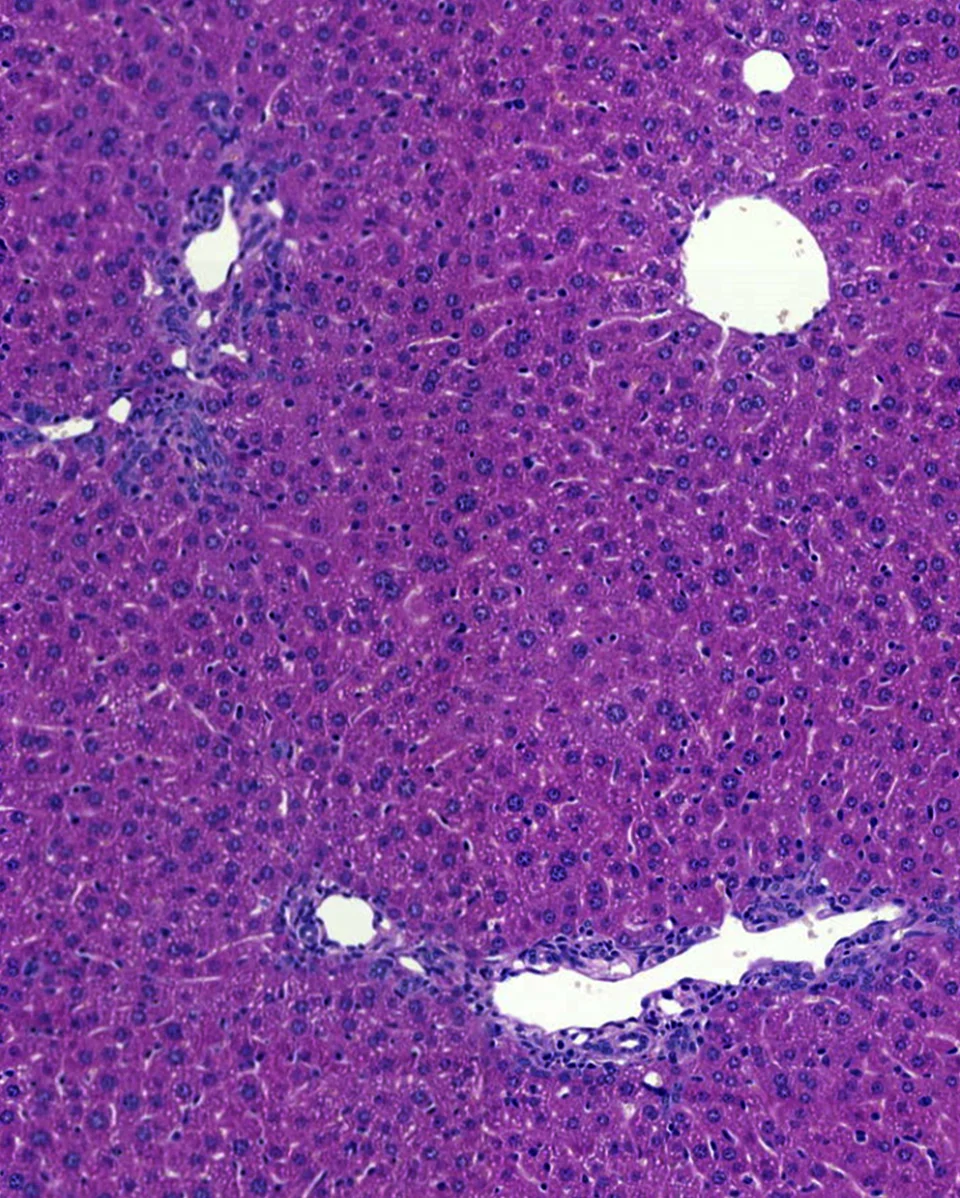

Notre objectif global est d’innover dans la prise en charge et le traitement des maladies du foie.

1. L’étude des mécanismes (génétiques, moléculaires et cellulaires) physiopathologiques, dans la perspective de découvrir des cibles thérapeutiques : cet axe traverse toutes les équipes de l’unité, mais il représente surtout le cœur des activités des équipes 3 et 4, dans le cadre des cancers du foie d’une part (équipe 3), et dans le contexte des maladies cholestatiques, de la stéatose et de la réparation du foie d’autre part (équipe 4) ;